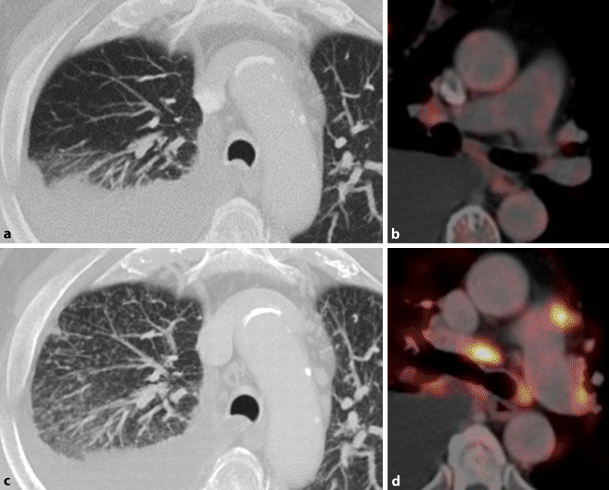

Fig. 1

Pseudoprogression in 54-year-old man with non-small cell lung cancer receiving immune checkpoint inhibitor therapy. a Coronary fluorodeoxyglucose positron emission tomopraphy/computed tomography (18F-FDG-PET/CT) imaging obtained before therapy demonstrate 18F-FDG avid malignant tumor in the right lung. b 5 weeks after treatment initiation tumor size and FDG uptake increased. Therapy was continued and 6 weeks thereafter tumor size shrinkage and a reduced 18F-FDG uptake were observed (c)